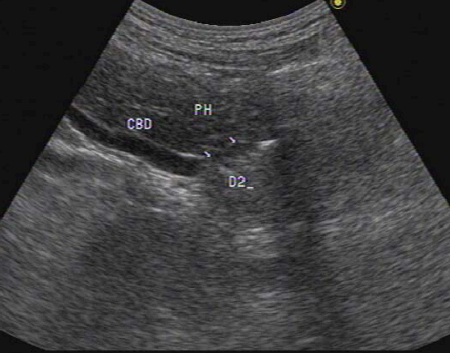

- 간외담관(extrahepatic bile duct)은 총 간관(CHD)과 총담관(CBD)으로 나뉘고 그 끝은 십이지장 내 유두부이다.

- 간외담관은 십이지장과 연동하여 연동운동을 보인다.

- 십이지장의 연동운동에 맞춰 유두 부네 담관의 개폐(open and close)를 확인한다.

- 간외담관에 대한 초음파검사는 유두부(vater's papilla)까지 묘출하는 것을 원칙으로 한다.